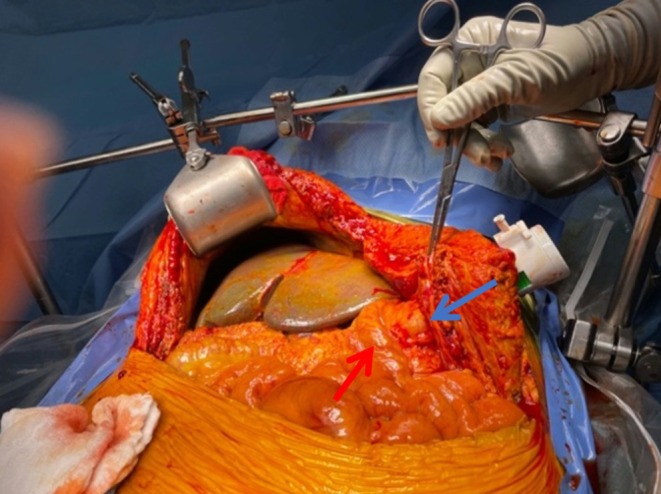

On POD9, given this amalgamation of findings, there was ongoing concern for biliary stricture. The decision was made to proceed to the operating room for exploration and interrogation of the biliary anastomosis. There were extensive newly formed inflammatory adhesions from the omentum to the upper anterior abdominal wall, as well as multiple older adhesions from the patient’s previous gastric bypass. They were all carefully lysed. The liver appeared cholestatic. No bilomas were seen. The hepatic artery was evaluated by intraoperative ultrasound and was wide open with excellent flow. The hepatic neo‐triad was inspected and noted to appear significantly inflamed and friable, thus making further dissection and possible surgical repair unsafe. Thus, the decision was made to conduct TG‐ERCP, given the patient’s RYGB anatomy.

To proceed with TG‐ERCP, the roux limb and gastric remnant were both identified and dissected. The gastric remnant was mobilized, and an abdominal wall incision was made in the upper left quadrant above the left extension of the Mercedes incision. A gastrotomy was made, and a 15 mm trocar was placed through it into the gastric lumen, as previously described (Figure 2) [ref. 14]. The anterior wall of the remnant was then stammed to the abdominal wall with a 3–0 barbed suture. The abdominal cavity was temporarily closed, and overlying drapes were placed, allowing access solely to the 15 mm trocar (Figure 3). The advanced endoscopist then cannulated the trocar with the side‐viewing endoscope, and an ERCP was performed in the usual fashion (Figure 4). A single biliary stricture was identified at the anastomosis, and a 10 cm, 7‐French plastic stent was placed across (Figure 5). No balloon dilation of the anastomosis was performed due to the recentness of the anastomosis. The trocar and the overlying drapes were removed, and a 24‐French gastrostomy tube (G‐tube) was placed through the gastrotomy for future biliary access and enteral nutrition, if deemed necessary. Liver biopsy was performed that demonstrated marked canalicular cholestasis and bile ductular proliferation consistent with the biliary obstruction. There was no evidence of rejection.